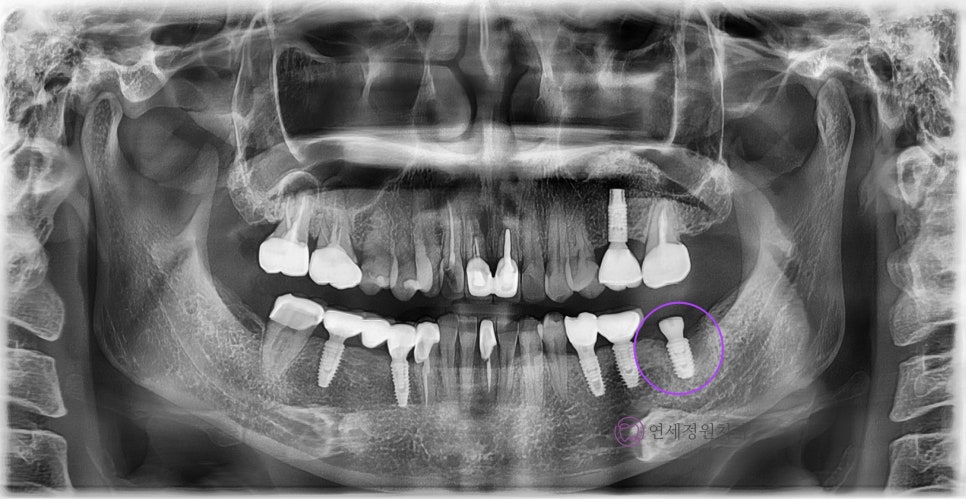

대치동 임플란트

위 엑스레이 사진과 같이 오른쪽 아래 어금니를 발치한 후 인공치근을 식립한 과정을 1차 수술이라고 합니다. 다른 부위에 식립한 임플란트와는 달리 치아의 뿌리에 해당하는 픽스쳐만 식립되어 있는 것을 확인할 수 있습니다. 이 인공치근이 잇몸뼈와 충분히 유착될 때까지 잇몸 아래 묻어두어서 안정적인 골유착을 유도합니다.

이 때 환자분의 잇몸뼈 상태나 식립한 임플란트 픽스쳐의 초기 고정 상태 등을 고려합니다. 환자의 잇몸뼈의 상태가 좋지 않거나 감염이 우려되는 경우, 또는 픽스쳐의 초기 고정력이 약한 경우, 어떠한 외부의 자극이 가해지지 않도록 커버 스크류라고 하는 작은 나사 뚜껑을 덮어서 잇몸 안에 픽스쳐를 묻어두어 골유착이 일어날 때까지 충분히 기다립니다. 추후 보철물을 연결하기 위해 잇몸 안에 묻어둔 임플란트 픽스쳐를 외부로 노출시키는 과정이 필요한데 이 과정이 바로 2차 수술에 해당합니다.

임플란트 2차 수술은 1차 수술 후 3~6개월의 골유착 과정을 거친 후 시행하며, 잇몸뼈와 인공치근(픽스쳐)이 잘 결합하였는지 확인하고 보철물이 올라가기 전에 잇몸의 모양을 잡아주기 위한 과정으로 생각하시면 됩니다. 약간의 잇몸 절개 후 잇몸으로 덮여 있던 임플란트를 노출시키며, 잇몸 회복을 위해 힐링 어버트먼트를 연결하여 치유 기간 동안 잇몸의 모양이 잘 잡히도록 도와주게 됩니다. 1차 수술 시 잇몸뼈의 상태가 좋고 임플란트 픽스쳐의 초기 고정이 잘 나올 경우에는 바로 힐링 어버트먼트를 연결하여 2차 수술이 생략되기도 합니다.